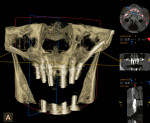

Closure of the maxilla was completed with a bone-hole suture technique to stabilize buccal and palatal flaps with 4-0 monocryl suture (Ethicon, ethicon.com), followed by a continuous sling suturing technique for the rest of the wound closure. Conversion of the immediate temporary denture was then completed, and it was retrofitted to the multi-abutments placed. The immediate postoperative CBCT scan facial view is shown in Figure 5. Appropriate A-P spread was obtained with the successful placement of the zygomatic implants.

The patient was given instructions to manage the postoperative healing phase. After an uneventful 5-month healing and maturation phase, the restorative clinician initiated impression techniques to fabricate the final All-on-4 zygomatic acrylic prosthesis with a titanium bar support. Figure 6 shows the occlusal surface of the definitive prosthesis with the correct placement of the zygomatic implants 6.5 months post-placement, which resulted in minimal thickness of the palatal aspect of the final implant-supported denture. Figure 7 shows the case-complete CBCT scan facial view with the titanium bar evident, 6.5 months post-placement. The patient was quite pleased with her new smile (Figure 8).